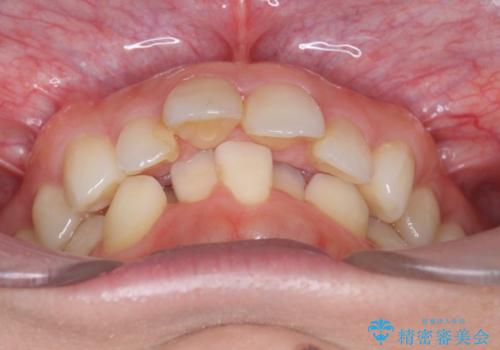

出っ歯 下の歯のガタガタ 下の前歯のみ1本抜歯 マウスピースで1年

- 出っ歯を主訴に来院。

航空会社勤務とのことで、矯正には会社の許可がいる上、許可を取るのが難しいだろうとのことでした。

育児休業中に矯正を終わらせることになりました。

下の前歯のがたつきがひどく、非抜歯では難しい状態でした。

古典的な方法では4本抜歯した後、ワイヤー矯正という方法も選択肢には上がりましたが、下の前歯を1本だけ抜くことにし、マウスピースで短期間で治療を終わらせるようにしました。

治療も比較的短期間で終わり、大変喜んでいただきました。

下の前歯を1本抜くと上下の正中はあいませんが、ほとんど目立ちません。